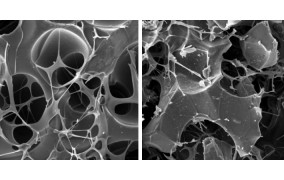

Com investimento da FAPESP, o Centro Avançado de Diagnóstico Molecular integra pesquisa básica e aplicada ao atendimento público; a partir da identificação de biomarcadores específicos, será possível detectar precocemente câncer e outras doenças